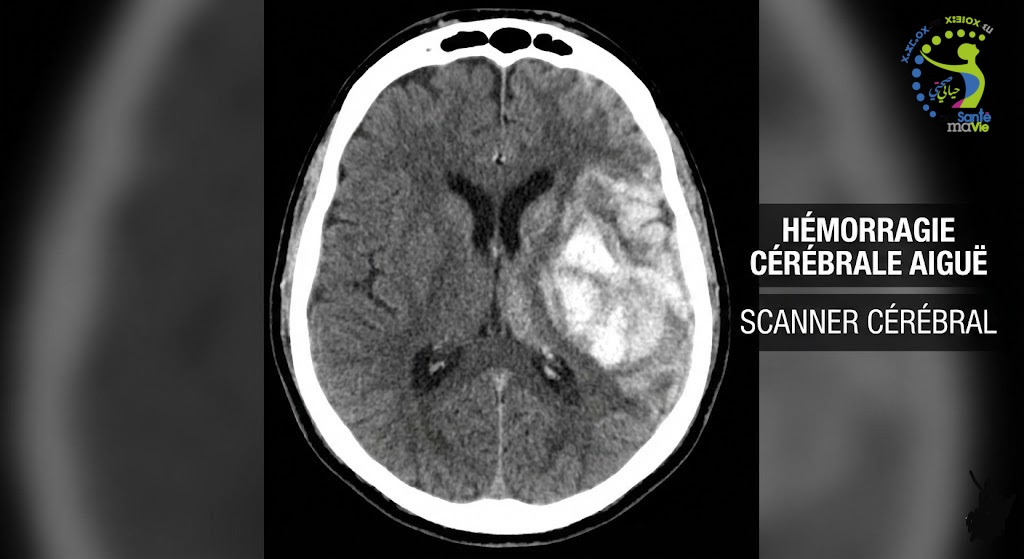

Diagnostic pour une hémorragie cérébrale

Pour diagnostiquer une hémorragie cérébrale, le médecin se base sur des examens d’imagerie médicale. Ces examens sont une IRM du cerveau ou encore une tomodensitométrie, pour localiser et mesurer l’importance de l’hémorragie cérébrale. Un bilan sanguin est de même effectué pour mesurer le taux de glycémie, de cholestérol et de coagulation (nombre de plaquettes).